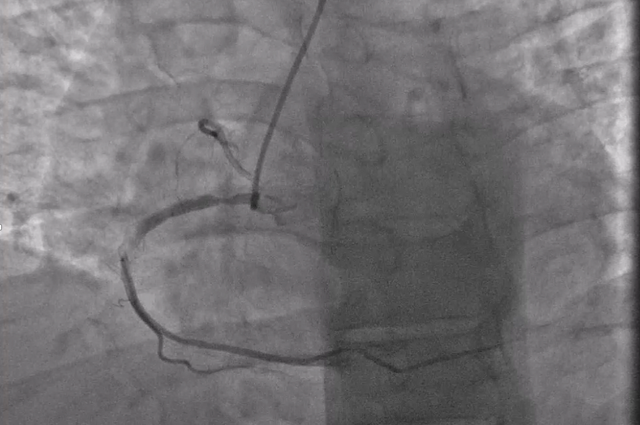

104 minutes later the patient was transferred to the cardiac catheterization laboratory where coronary angiography was performed that revealed an 80% stenosis of the proximal right coronary artery and a 90% stenosis in the mid-right coronary artery (Figure)